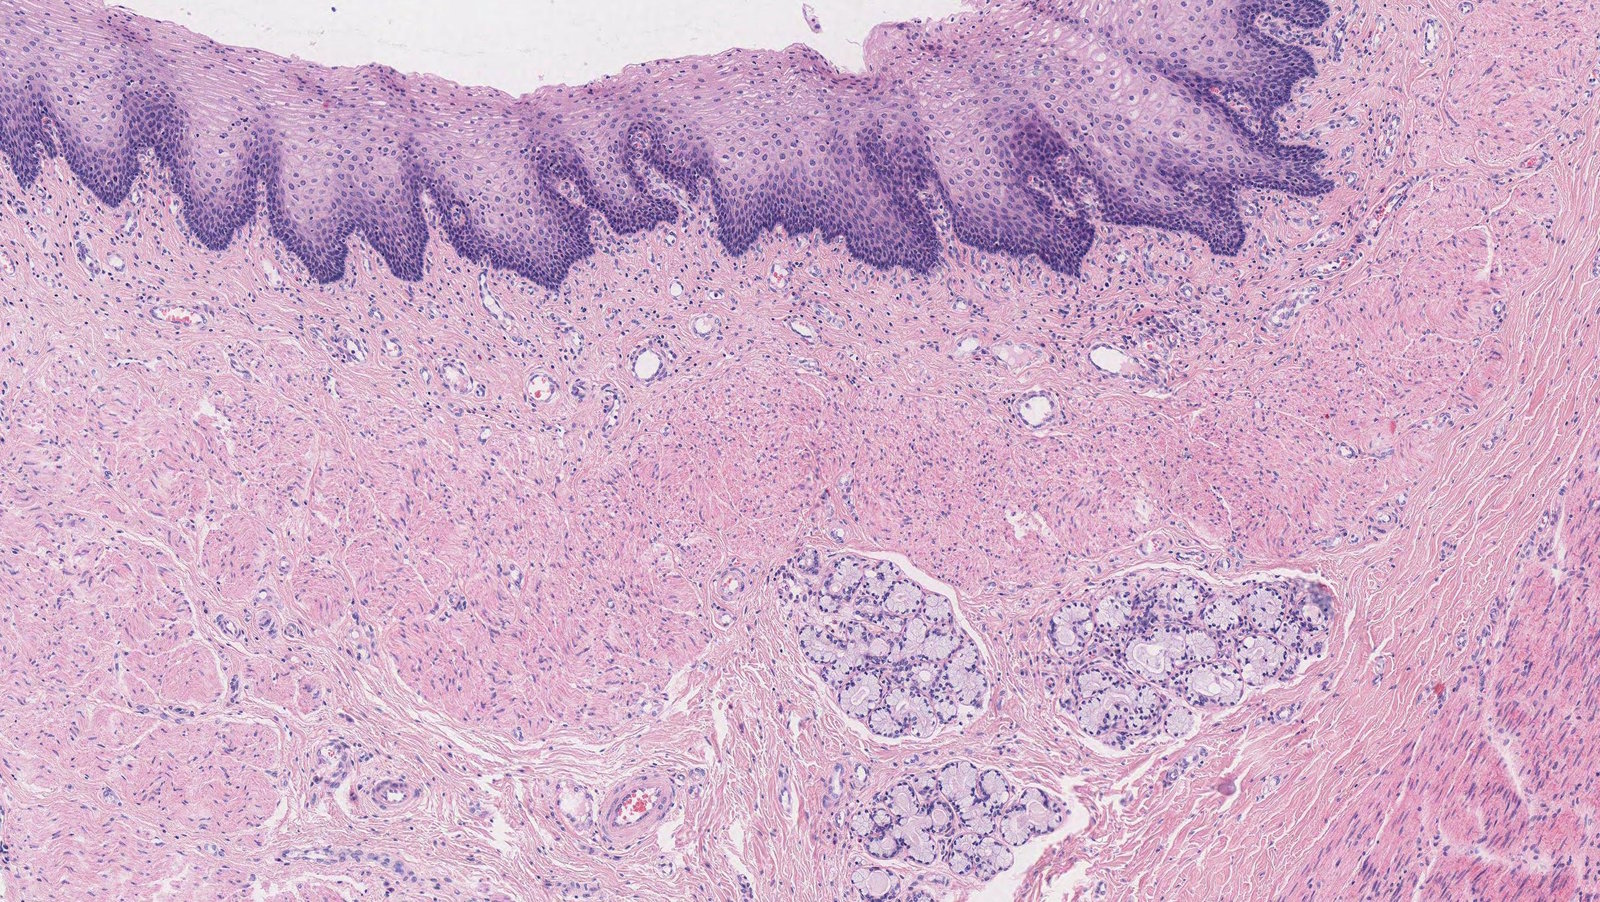

• Four concentric layers

• Mucosal (innermost)

• Nonkeratinizing stratified squamous epithelium

• Transitions to columnar epithelium at the gastroesophageal junction